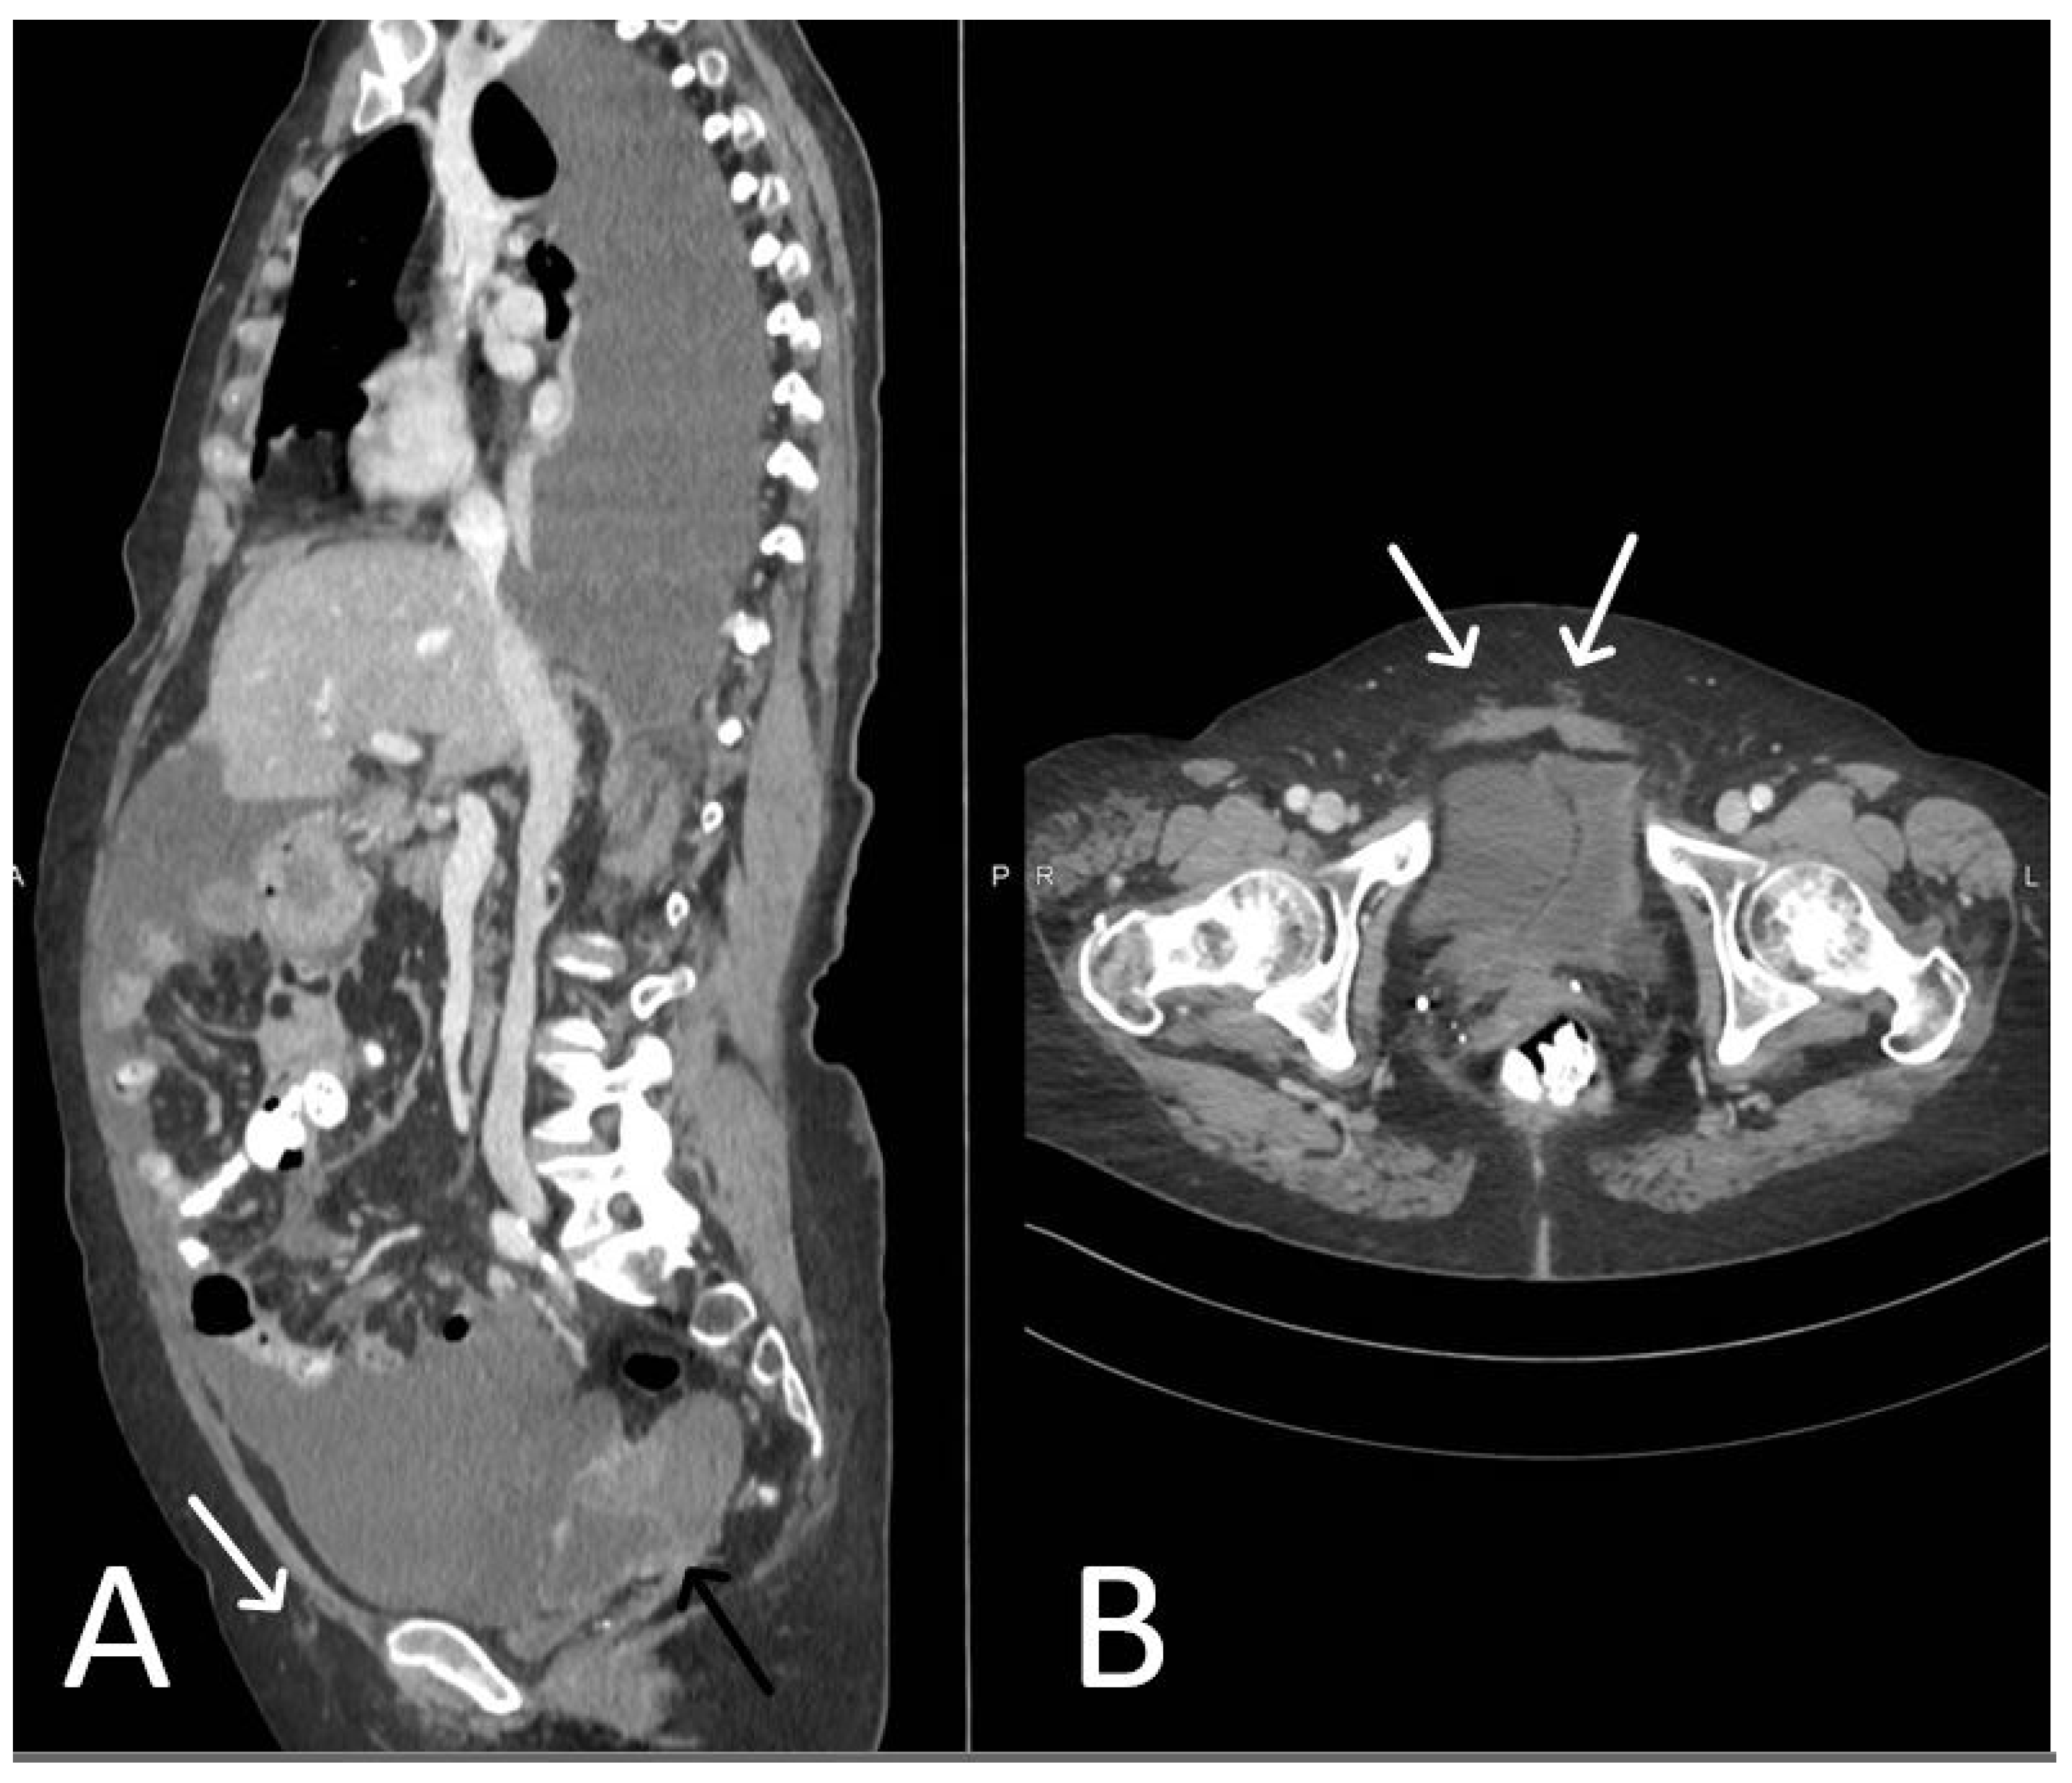

4. Urethral Mesh in Oncological Patients

5. Urethral Mesh Complications